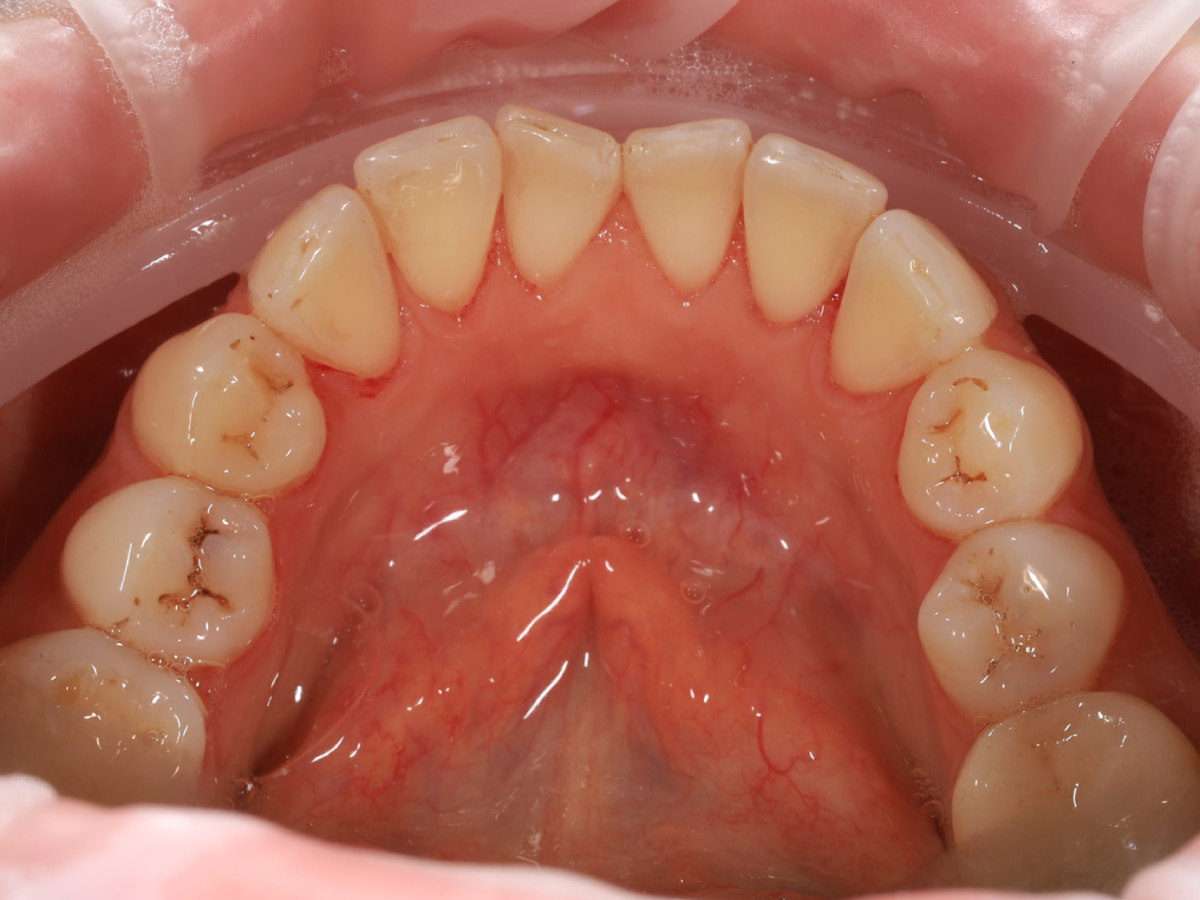

Pełna higienizacja: usunięcie kamienia i osadu (scaling, piaskowanie).

Metamorfoza uśmiechu: usunięcie przebarwień i kamienia nazębnego.